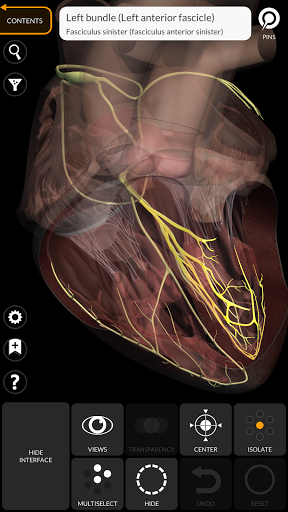

يتيح لك "Anatomy 3D Atlas" دراسة التشريح البشري بطريقة سهلة وتفاعلية.

من خلال واجهة بسيطة وبديهية، من الممكن ملاحظة كل بنية تشريحية من أي زاوية.

تتميز النماذج التشريحية ثلاثية الأبعاد بتفاصيل خاصة ودقة تصل إلى 4K.

• الجهاز القلبي الوعائي

• الجهاز العصبي

• وظيفة الشفافية